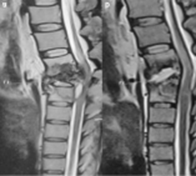

7. Subtopic: Musculoskeletal Infections

Question Number: 2

Clinical question

A 40-year-old male presents with chronic back pain that has progressively worsened over the past few months. He also reports fever, night sweats, and unintentional weight loss. On examination, there is localized tenderness over the lower thoracic and lumbar spine. MRI spine is shown below. What is the most likely diagnosis? (Medicine)

Options:

- Pott’s spine

- Osteoporotic vertebral fracture

- Metastatic spinal tumor

- Ankylosing spondylitis

Correct Answer: A) Pottβs spine

Get the full explanation here: https://www.doctutorials.com/fmge/qbank/pyq/1000119